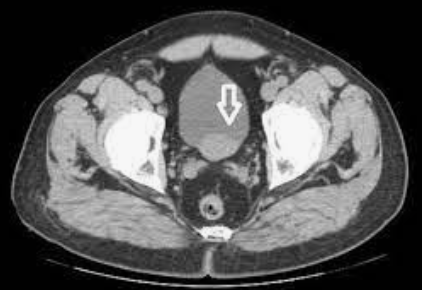

47

Trauma

Think extrapeitoneal bladder rupture and recommend cystography or delayed/excretory phase imaging Note: This is the "molar tooth" sign of extraperitoneal bladder rupture.

48

Molar tooth sign of extraperitoneal bladder rupture is due to contrast accumulation in what potential space?

Prevesicle space of Retzius